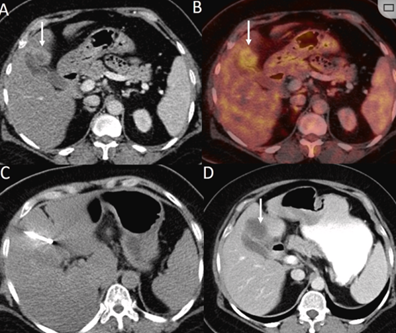

膽囊附近轉(zhuǎn)移灶(來自子宮頸癌)的冷凍消融術(shù)(A)門靜脈期 CT 圖像顯示膽囊附近有病變(箭頭)。(C) 手術(shù)過程中CT 顯示冷凍探針位于病灶內(nèi)。(D)消融手術(shù)后 1 個(gè)月CT 顯示完全消融。

本研究中患者隨訪期間無局部腫瘤進(jìn)展,無死亡病例,沒有發(fā)現(xiàn)與手術(shù)相關(guān)的并發(fā)癥。證實(shí)冷凍消融是一種有效的治療方式,在技術(shù)上是可行和安全的。由于肝包膜下病變位置特殊,射頻消融有出血及腫瘤種植的風(fēng)險(xiǎn),可能會對鄰近器官造成損傷,并且增加局部腫瘤進(jìn)展的風(fēng)險(xiǎn)。近年來,冷凍消融術(shù)的應(yīng)用逐漸廣泛,有研究顯示冷凍消融治療具有明顯優(yōu)勢,可治療特殊部位的肝腫瘤。本研究的目的是評價(jià)冷凍消融治療肝包膜下腫瘤的安全性和有效性。回顧性納入2016年7月1日至2018年9月1日期間冷凍消融的57例患者。包括42例男性和15例女性,平均年齡為62.4歲(范圍:48-82歲)。每個(gè)患者有1個(gè)或2個(gè)平均腫瘤尺寸為2.4cm的病變(范圍:0.6-4.0cm)。所有患者均患有慢性肝病或肝硬化,并伴有乙型肝炎(n=52)、丙型肝炎(n=3)和其他肝炎(n=2)。根據(jù)腫瘤位置,在膈肌或肝臟下附近有18個(gè)病變(26.5%),胃或腸附近有9個(gè)病變(13.2%),腹壁附近有33個(gè)病變(48.5%),腎臟附近有8個(gè)病變(11.8%)。

(a) 射頻消融后在病變邊緣顯示殘余增強(qiáng)。(b) 冷凍消融術(shù)中影像顯示冰球完全覆蓋病變。(c) 19個(gè)月后隨訪,沒有發(fā)生局部腫瘤進(jìn)展。完全消融率為97%(66/68);2名患者均接受了額外的冷凍消融,隨后實(shí)現(xiàn)完全消融。平均隨訪期為 12.8 個(gè)月(范圍:3-27 個(gè)月)。所有患者均接受影像復(fù)查(CT 或 MRI)。11個(gè)病灶(16.2%)檢測到局部腫瘤進(jìn)展,6、12和18個(gè)月時(shí)的累積局部腫瘤進(jìn)展率分別為4%、8.2%和20.5%。8例出現(xiàn)遠(yuǎn)處肝內(nèi)或肝外病變的患者接受經(jīng)動(dòng)脈化療栓塞、經(jīng)動(dòng)脈化療栓塞加射頻消融治療或全身化療。